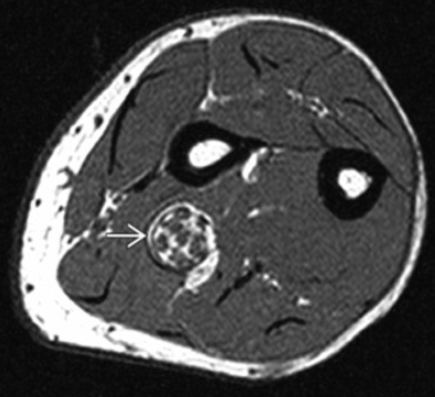

Lipomatosis of Nerve

• Basically fatty infiltration of the nerve

• If occurs in median nerve will result in thenar atrophy similar to carpal tunnel syndrome

• Has the coaxial cable appearance

• If you see fat in the lesion it excludes a neurofibroma or schwannoma which are other items in the ddx